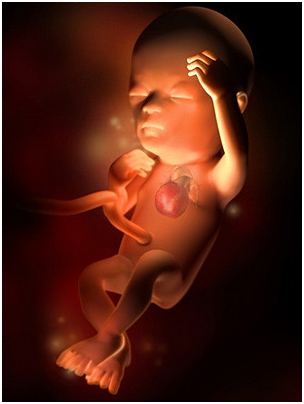

怀孕第28周胎儿图 从现在开始,你就进入了孕晚期,要注意的事情很多呦!你要每天做胎动...

怀孕第28周胎儿图 从现在开始,你就进入了孕晚期,要注意的事情很多呦!你要每天做胎动... -